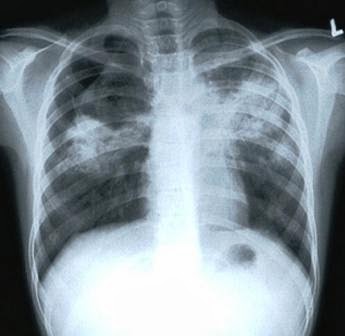

¿Cómo se diagnostica?

El diagnóstico se basa en

la radiología (habitualmente radiografías

torácicas), una prueba de la tuberculina

cutánea y análisis de sangre, así como un

examen al microscopio y un cultivo

microbiológico de los fluidos corporales como

las espectoraciones.